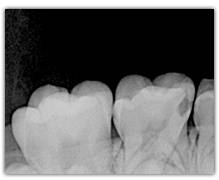

What represent the white, blue, red or black areas which can been seen on the tooth?

According to the pathologies of the tooth (destructured enamel, affected dentine, anfractuous fissure, presence of a crown…), the signal of fluorescence of the dentine will be different (weaker, darker, redder, absent…)

The spectrum of the signal of fluorescence (let’s call it "its color") is rather in the green when the dentine is healthy and red/dark when the dentine is infected.

The light must cross the enamel to excite the dentine. Following this excitation, the dentine send back a signal of fluorescence which must cross the enamel to be interpreted. The thicker the enamel is, the weaker the signal of fluorescence is. The intensity of the green light will be weaker and gradually tinted with blue (because of the way through enamel). This is the case for the cusps